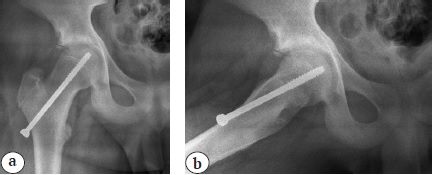

Техника операции

Все дети получили хирургическое лечение, заключающееся в фиксации проксимальных эпифизов обеих бедренных костей с использованием электронно-оптического преобразователя (ЭОП) рентгеновского изображения. Для фиксации применялись самонарезающие канюлированные винты диаметром 7,0 мм с наружной резьбовой нарезкой на конце, занимающей около одной четверти общей длины. Винт вводился в эпифиз с передненаружной поверхности бедренной кости через шейку и центр ростковой пластинки, при этом головка винта не опиралась на кортикальный слой, а отстояла от бедренной кости на 5–10 мм (рис. 1).

Рис. 1. Рентгенограммы правого тазобедренного сустава в переднезадней проекции (а) и в проекции Лауэнштейна (b) пациента 13 лет 11 мес. непосредственно после операции. Объяснение в тексте

Всего проведено 64 подобные операции — каждый ребенок оперирован на обоих тазобедренных суставах в одну хирургическую сессию. Во всех наблюдениях металлоконструкции удалялись после завершения синостозирования эпифиза и метафиза — в возрасте от 17 до 18 лет.